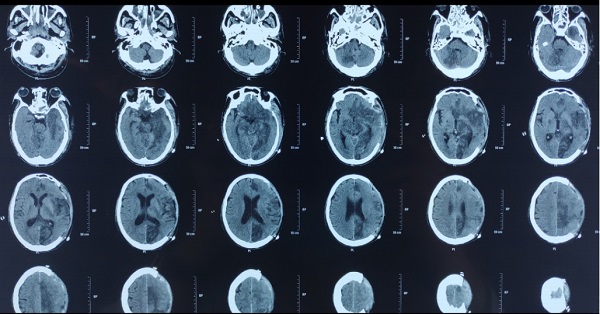

57岁谭先生3天前不慎摔伤,当时自觉无特殊不适感,并未在意,直至出现头痛、呕吐症状才就诊当地县医院,头颅CT检查提示急性硬膜下血肿,此时意识已处于深昏迷状态,双侧瞳孔大小不等。接到医院急诊的电话,神经重症卒中监护室谢国强副主任立即带领科室医生到急诊科,等待患者到来,患者入急诊科后,立即开通绿色通道,争分夺秒,为急诊手术做准备。此时头颅CT提示急性硬膜下血肿,量约100ml,诊断为脑疝。